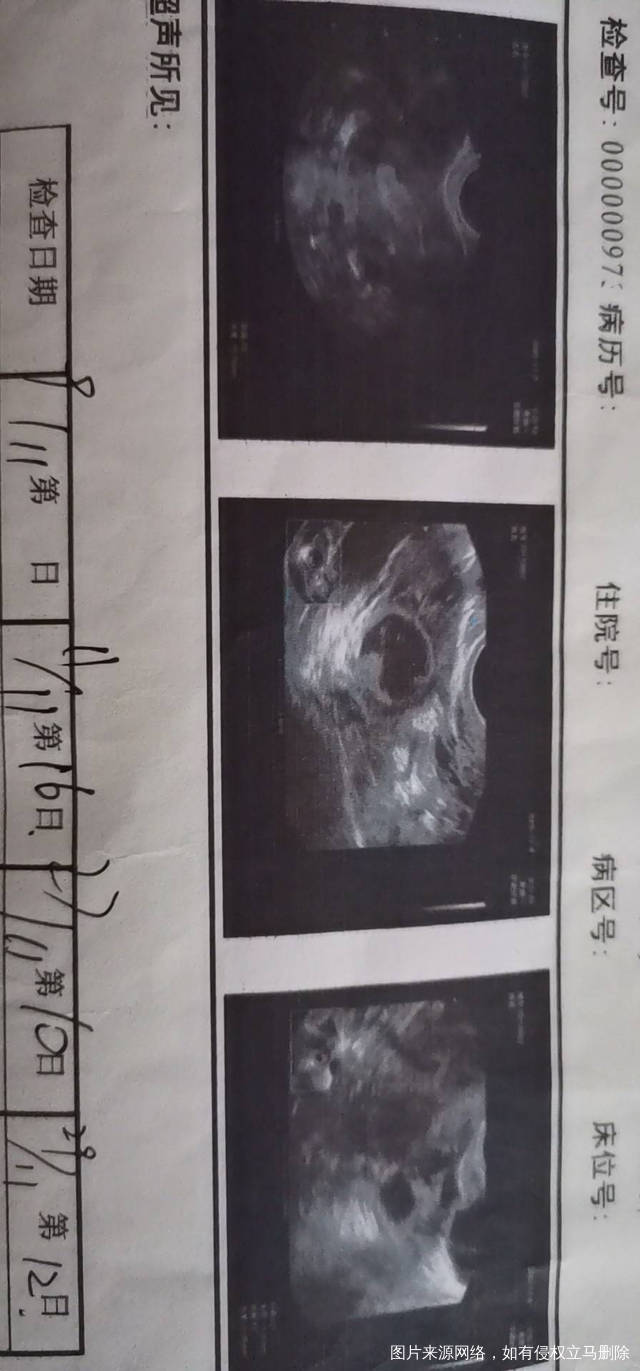

可看清肌瘤长在哪里吗